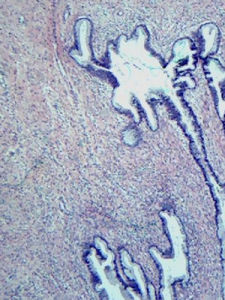

1.子宮頸上皮內瘤變(CIN)子宮頸癌是最常見的婦科惡性腫瘤,是感染性癌瘤,是可以預防、可以治癒的癌瘤。1967年Richart提出子宮頸上皮內瘤變的概念,包括了細胞不典型增生和原位癌。CIN發展為原位癌、浸潤癌的風險分別是正常的20倍和7倍。ACOG(美國婦產科醫師學會)建議:所有有性活動或年齡超過18歲的婦女每年都應進行一次宮頸細胞學檢查。當連續三次或以上的檢查均獲滿意且結果正常,可酌情減少檢查次數。2.外陰上皮內瘤樣病變(VIN)外陰上皮內瘤樣病變是發生在外陰鱗狀上皮內的一種癌前病變,VIN包括以往舊稱為外陰非典型增生、原位癌、鮑溫病和凱臘增殖性紅斑等,但不包括非鱗狀上皮的上皮內病變,例如原位黑色素瘤、Paget’s病等。1987年,ISSVD(國際外陰陰道疾病研究協會)與國際婦科病理學會研究決定,對常見的外陰癌前病變加以命名與分類。外陰原位癌為外陰上皮內癌或侵襲前癌,病變可波及上皮全層,但未侵犯真皮,其生長緩慢,外觀可見有多種表現,如紅褐色丘疹、鱗屑性斑塊樣病變、肉芽腫、白斑樣或雜色微高於皮膚面等病變。3.胰管上皮內瘤變在胰腺導管癌的周圍常可見胰管上皮的增生和不典型增生。近年引進的胰管上皮內瘤變(PanIN)的概念把各種胰管上皮增生性變化均收入其內。PanIN1A為最輕的一種,所包含的有過去稱之為黏液細胞化生或黏液細胞肥大和單純性增生這樣一些導管上皮的增生狀態。PanIN其實很常見,在很多情況下均可見到,但當在胰腺標本中見有PanIN2和PanIN3的病變時應註明。4.陰莖上皮內瘤變陰莖上皮內瘤變(PIN)是癌前病變的組織譜,與女性生殖道的女陰、宮頸的同名病變相對應,表現為上皮成熟障礙、細胞極性異常及核的非典型性。過去曾名為輕、中、重度異型增生,以及原位癌。目前採用陰莖上皮內瘤變Ⅰ、Ⅱ、Ⅲ,也有採用陰莖鱗狀上皮內病變,高、低級別者。Queyrat紅斑或Bowen病相當於高級別鱗狀上皮內病變或鱗狀上皮原位癌。Queyrat紅斑臨床上常用於龜頭及包皮,而Bowen病常用於陰莖體。WHO把巨大尖銳濕疣看作陰莖癌前病變。5.結膜上皮內瘤變結膜上皮內瘤變(CIN)系指結膜上皮內局限性腫瘤性增生性病變。此類病變屬於癌前病變,包括過去診斷的結膜上皮非典型增生和原位癌。本病是結膜比較常見的上皮性腫瘤,因為少數病變會發展為浸潤性鱗狀細胞癌,故屬於癌前病變。6.結直腸上皮內瘤變結直腸腺瘤是臨床上最常見的一種息肉,也可稱為上皮內瘤變,具有組織結構和細胞學上的異型性,換而言之,若沒有組織結構和細胞學上的異型性則不能診斷為腺瘤。結直腸腺瘤與結直腸癌的關係密切,據統計,約80%結直腸癌源自腺瘤惡變。參考資料黃曉赤,羅克樞.上皮內瘤變.現代臨床醫學.2008(3).